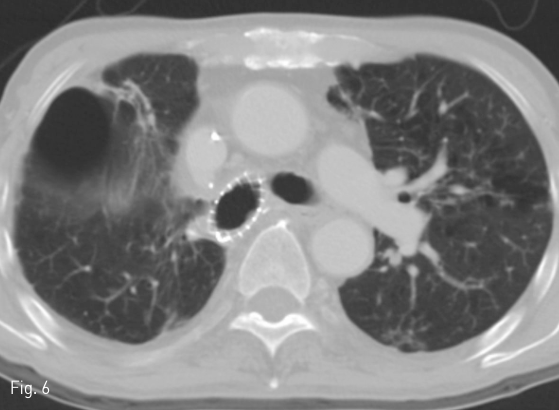

시술 약 4개월 뒤 시행한 추적 흉부 CT에서 stent가 위치 이동 없이 이전 기관흉막루가 있던 우상엽 stump를 완전히 덮은 것과 이전에 보이던 주변 air collection이 없어진 것(Fig. 6), 그리고 우중엽기관지 및 우하엽기관지를 막지 않고 있는 것을 확인하였다. 시술 후 환자는 호흡곤란이 호전되었고, stent로 인한 pain 등의 증상이 없고 위치이동이 없어서 retrieval은 하지 않고 추적 관찰하기로 하였다.

Fig 6

Chest CT taken 4 months after the procedure shows occlusion of the previously visualized bronchopleural fistula with disappearance of the adjacent air collection.